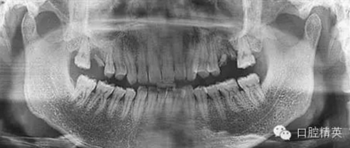

曲斷銳化后

3個月后來進行種植手術,頜骨曲面斷層片

檢查口腔種植區(qū)骨和粘膜厚度為7.5MM。齦顏色正常,無瘺道。種植區(qū)牙槽骨密度接近正常,竇嵴距10MM,左上頜竇無明顯炎癥影像。排除曲斷這個位置的20%放大率,擬做上頜竇內提升后種植ITI的10MM的種植體。